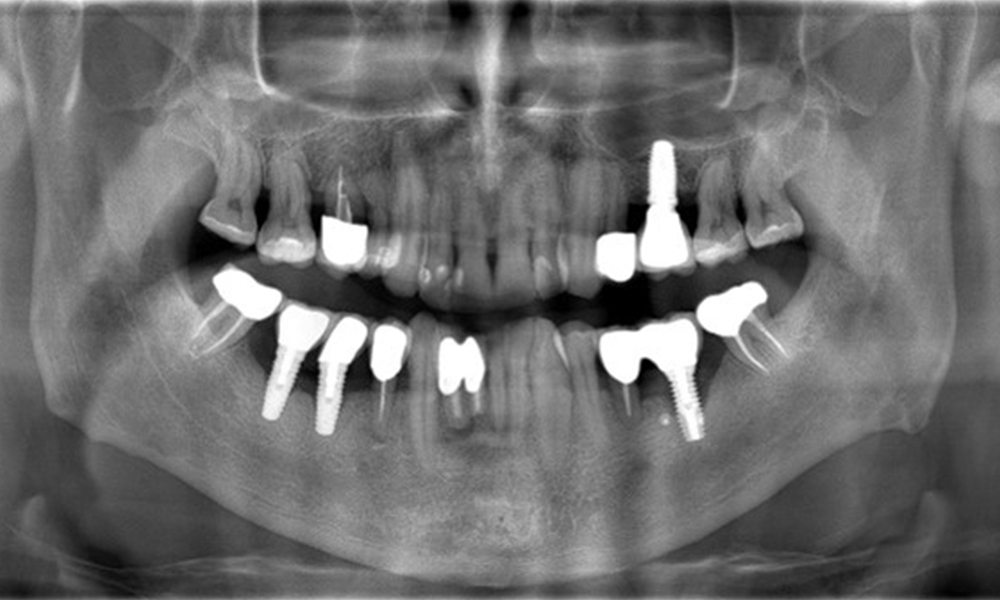

Ein 52-jähriger Patient stellt sich zur Präventionssitzung vor. Der Patient hat keine Allgemeinerkrankungen und nimmt keine Medikamente ein. Er hat verschiedene zahnärztliche Versorgungen und zudem zwei aktive kariöse Läsionen. Außerdem verfügt der Patient über vier Implantate (2., 3. und 4. Quadrant). Es zeigt sich eine parodontale Vorerkrankung (Stadium IV, Grad B). Derzeit herrschen stabile parodontale Verhältnisse, lediglich am Implantat regio 36 zeigen sich Sondierungstiefen (ST) von 5 mm. Zudem lässt sich eine Gingivitis feststellen.

Der Patient zeigt keine besonderen anamnestischen Risikofaktoren mit spezifischen zahnmedizinischen Auswirkungen. Daher ist der aus der Mundgesundheit ermittelte Bedarf maßgebend. Hierbei zeigt sich am Implantat im 3. Quadranten ST von 5 mm und im Röntgenbild eine Zunahme des Knochenverlustes. Der Patient hat zudem eine aktuell stabile parodontale Vorerkrankung und zwei aktive initialkariöse Läsionen.

Röntgenaufnahme zeigt Verlauf des Knochenabbaus

"Die Röntgenaufnahmen zeigen den Verlauf des Knochenabbaus. OPG vom 29.06.2020 (links) und OPG vom 26.02.2024 (rechts)